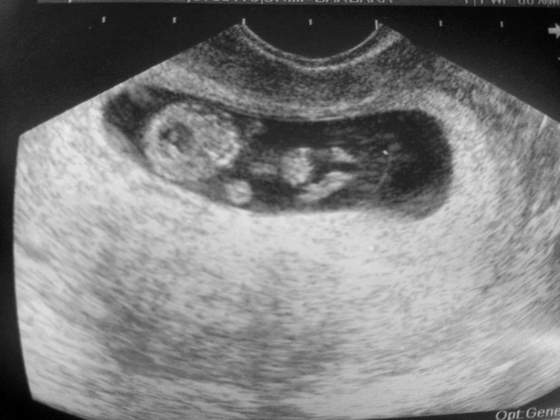

Tak jak obiecalam dziewczyny. Kolejne fotki mojej modelki/ modela ♡ Z dzisiaj tj. 9+2. Moja nowa milosc ma 27,05mm :-):-):-)

Zobacz załącznik 564201Zobacz załącznik 564200